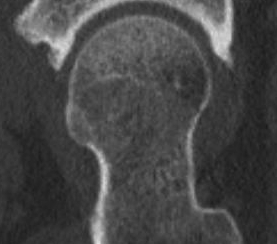

An MRI is very accurate at diagnosing a labral tear and any extra bone which may be contributing to the problem, such as a CAM (extra bone on the femoral side) or pincer (extra bone on the pelvis or acetabular side). Even more importantly, an MRI will look at the cartilage covering the femoral head (ball) and the acetabulum (socket). If you have significant cartilage damage, it is likely that a hip arthroscopy will not help. In this setting, injections of PRP or Hyaluronic acid may be used to treat your pain. Otherwise, a total hip replacement may be required.